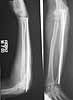

This patient,a middle aged malewas a diagnosed case of hypophosphatemic osteomalacia on treatment. Unfortunately he discontinued treatment since he was poor and also neutral phosphate was not available locally. He presented with pathological fracture of left femur and a failing neck of same femur.

We managed to get neutral phosphate, initiated medical treatment and did an antegrade SIGN nailing of left femur along with couple of screws to neck using miss a nail technique. He complained of pain of the right femur and both forearms. In OT these areas were screened using image intensifier and found that he has looser zones of all these with impending fractures. Yesterday we did a retrograde nailing of right femur usingSIGN nail. Both ulnas were stabilised usingLambrudini wires in a closed fashion. All fractures and looser zones were stabilised by closed surgery using image intensifier. It may be interesting to see the post of picture of both the hips in which one side shows an antegrade femoral SIGN nail and the other side shows a retrograde SIGN nail.